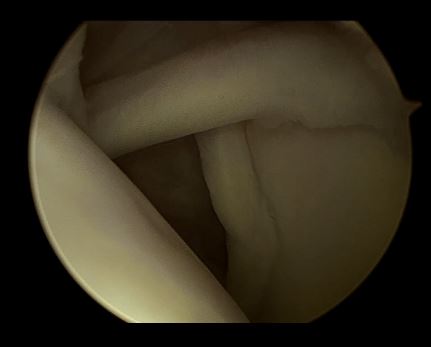

正常的肩关节 ——干净

关节镜下可以彻底的清理关节内炎性滑膜组织及黏连带(盂肱关节及肩峰下关节)

清理后 ,肌腱活动度明显改善